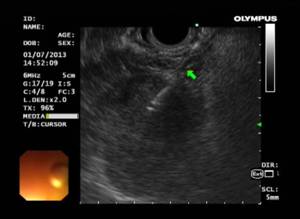

Во время лайф-демонстрации эксперты выполнили уникальные эндоскопические диагностические процедуры и лечебные операции: двум пациентам по поводу доброкачественного и злокачественного стеноза желчных путей были выполнены ЭРХПГ, ЭПСТ инструментом Boston Scientific, стентирование самораскрывающимся нитиноловым стентом BS Wallflex, трем пациентам с доброкачественными предраковыми заболеваниями толстой кишки были выполнены резекции слизистой оболочки и диссекции в подслизистом слое с патологическими образованиями, выполнено 3 эндосонографии с выполнением тонкоигольной аспирационной биопсии иглами BS Expect и последующими комментариями врачей-цитологов, в одном случае проведено чрезкожное атеградное дренирование желчных путей по поводу механической желтухи и билиарной гипертензии с помощью стента BS Wallflex, впервые в Ярославской области выполнена эндоскопическая крикофарингеальная миотомия по поводу дивертикула Ценкера, также в одном случае выполнено стентирование пищевода частично покрытым нитиноловым самораскрывающимся стентом BS Wallflex.